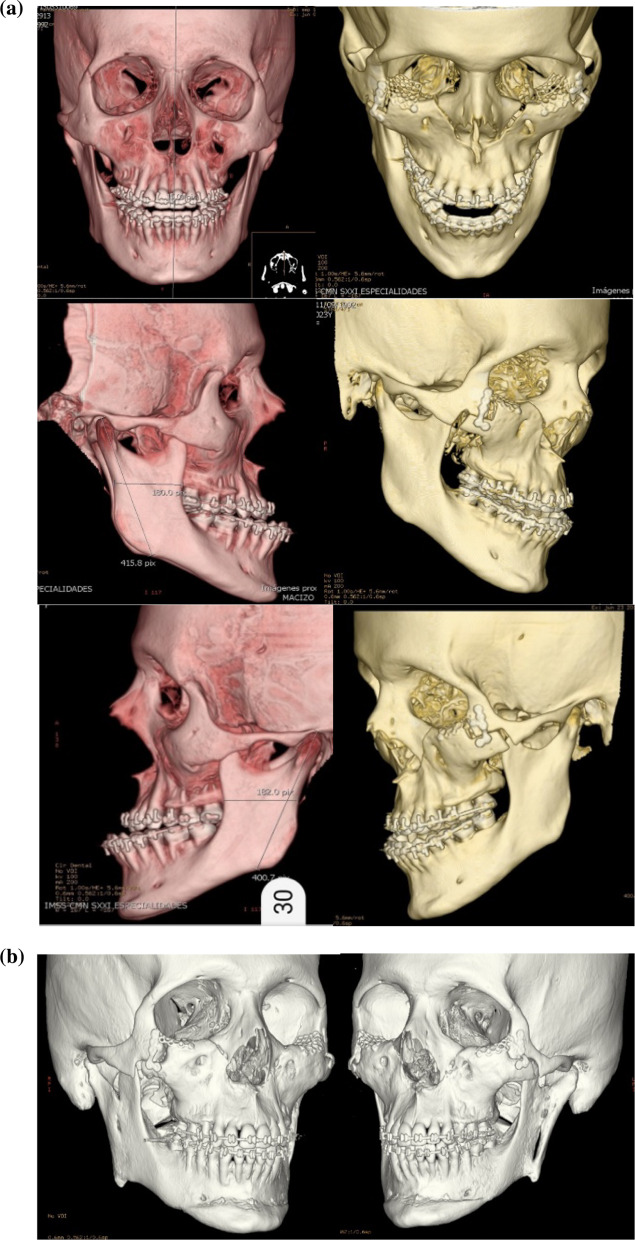

24-year-old male patient with severe midface deficiency. The first surgery was a MAZLFIIIO with a 6 mm advancement through a coronal and transconjunctival approach. He had a posteroanterior discrepancy of 11 mm as shown in the preop lateral radiograph. On the second surgery, a 4 mm advancement Le Fort I osteotomy was performed along with an intraoral inverted L oblique modified osteotomy (IILOMO) with a 3 mm mandibular setback. A basal extended mentoplasty [16] (BEM) of 8 mm was also performed on the patient. The preop and postop lateral radiograph are shown. The 1-day postop CT scan with osteotomies and rigid internal fixation is also shown in Fig. 23a. The preop CT scan and the 2-year postop CT scan of the same patient are shown in Fig. 23b. A symmetric midface advancement with adequate bone consolidation is shown. The IILOMO is shown with adequate bone consolidation and the BEM adds harmony to the basal portion of the mandible without steps, appreciated in Fig. 23b.

Fig. 23.

a Pre- and post-operative lateral radiograph. Significant changes in the midface and lower third of the face can be seen. CT reconstruction immediately following the second surgery. A symmetric MAZLFIIIO can be appreciated along with a simultaneous repositioning of the maxilla, mandible and chin. b CT reconstruction in frontal and lateral views. 3D reconstruction at 2 years postop

21-year-old male patient with severe midface deficiency. The first surgery was a 6 mm in advancement MAZLFIIIO through a transconjunctival with lateral canthotomy approach. The patient had a -10 mm overjet. After surgery, orthodontic treatment was indicated, and a second surgery was performed. The patient underwent an intraoral vertical subsigmoid osteotomy (IVSO) with a 6 mm setback and a BEM with an 8 mm advancement. The preop and postop CT scan demonstrates the MAZLFIIIO. Symmetry can be appreciated at the osteotomy sites, achieved through surgical guides (Fig. 26a).

Fig. 26.

a CT scan with 3D reconstruction preop and postop. Note the symmetry of the osteotomies. b 1-year postop 3D reconstruction. Adequate bone consolidation of the midface can be seen, achieving stability and symmetry of the MAZLFIIIO. The IVSO is adequately adapted. The BEM is also adequately consolidated to the mandibular body

A CT scan 1 year postop demonstrates a stable and symmetric midface advancement. The blue arrows indicate the zygomatic arch as one piece without any gaps. The IVSO is shown with adequate bone consolidation; however, the left proximal segment was displaced 3 mm lateral of the articular cavity. Nevertheless, the patient is asymptomatic. The BEM allows for an adequate facial harmony at the inferior border of the mandible without any steps, seen in Fig. 26b.